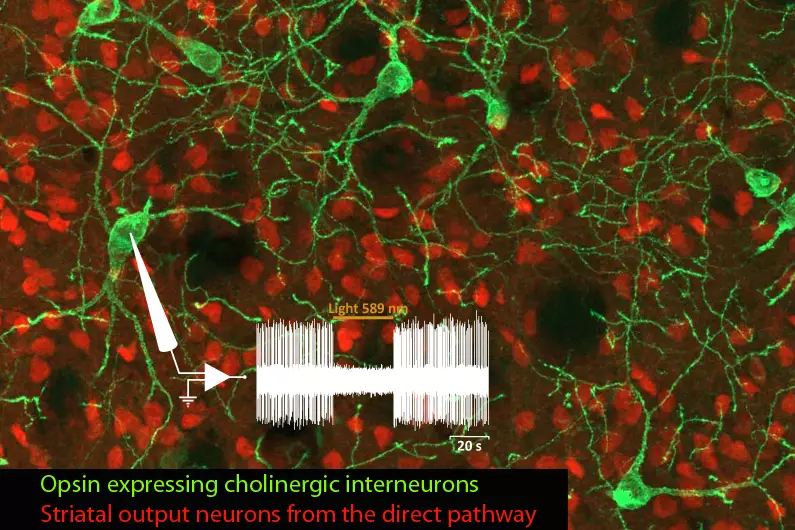

Notre principal intérêt de recherche porte sur la transmission synaptique, la neurodégénération et la neuroplasticité dans le cerveau adulte. La communication entre les neurones au niveau de leurs connexions, appelées synapses, est le substrat du traitement de l’information dans les réseaux qui sous-tendent les fonctions cérébrales. La transmission synaptique est un processus hautement dynamique et régulé, influencé par les cellules gliales, dont les anomalies sont associées à un certain nombre de maladies cérébrales (notion de synaptopathies). Neurodégénérescence est un processus pathologique qui déclenche le dysfonctionnement et la mort progressive des cellules nerveuses. La compréhension des mécanismes pathologiques qui déclenchent et entretiennent la neurodégénérescence (pathogenèse), de ses conséquences sur le fonctionnement des circuits et des mécanismes qui aident les neurones à gérer le stress cellulaire est essentielle pour le développement de traitements curatifs ou modificateurs de la maladie pour les troubles neurodégénératifs dévastateurs, tels que la maladie de Parkinson (MP). Neuroplasticité. désigne la capacité du système nerveux à s’adapter en réponse à l’expérience et aux stimulations internes ou externes en modifiant les interactions entre les cellules nerveuses, y compris les changements dans le nombre de synapses et l’efficacité/la force de la transmission synaptique (plasticité synaptique), ou en générant de nouvelles cellules nerveuses. Cette faculté n’est pas limitée au développement, mais se produit tout au long de la vie, bien qu’elle diminue avec le vieillissement. La neuroplasticité a notamment été impliquée dans les processus d’apprentissage et de mémoire. Elle se produit également dans des conditions pathologiques ou en réponse à des traitements chroniques. Ces changements adaptatifs peuvent représenter des mécanismes compensatoires contrecarrant les déficits déclenchés par le dysfonctionnement ou la mort neuronale, retardant l’apparition des symptômes, ou, au contraire, participer à ces déficits, voire les aggraver.

L’équipe étudie ces processus dans le contexte des fonctions et des pathologies liées aux ganglions de la base (BG), en particulier la MP, un trouble du mouvement caractérisé par la dégénérescence des neurones dopaminergiques du mésencéphale innervant le striatum, la principale station d’entrée des BG. Par le biais de collaborations, nos travaux abordent également des questions fondamentales et cliniquement pertinentes dans le contexte d’autres neuropathologies, notamment les troubles du spectre autistique (TSA), la maladie d’Alzheimer et la maladie de Charcot-Marie-Tooth.